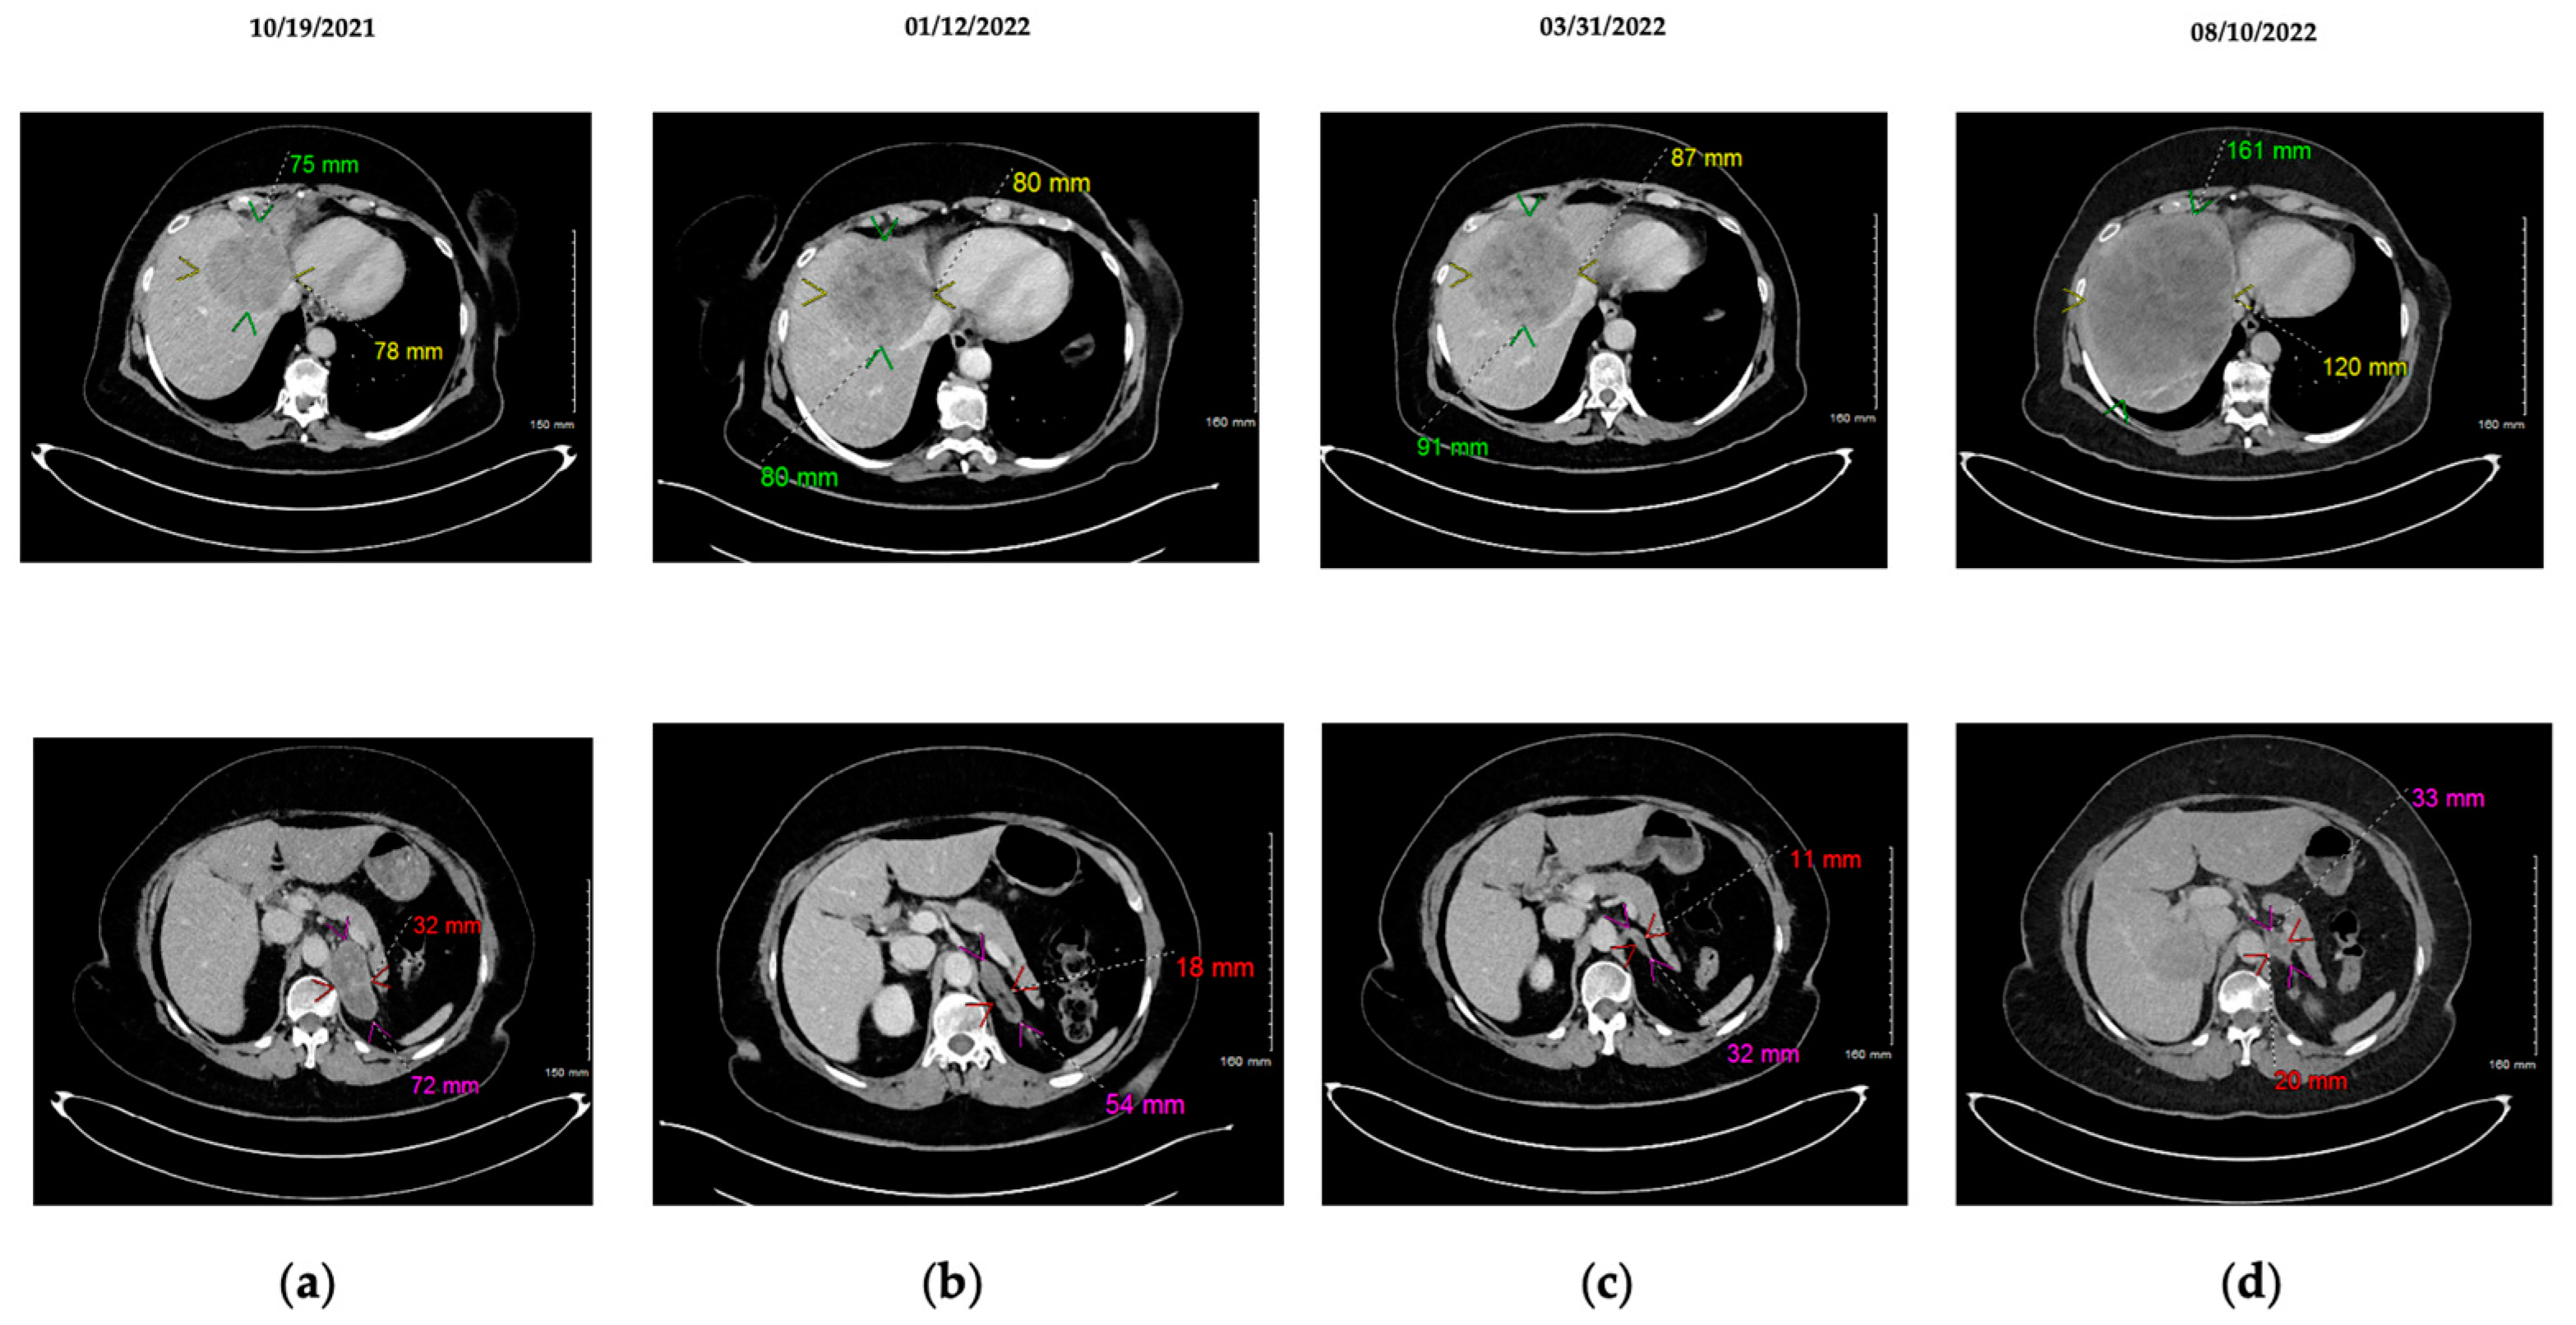

Figure 2. Hepatic (top) and adrenal (bottom) CT-scan illustrating tumoral evolution with combination of tyrosine kinase inhibitors. (a) Baseline with osimertinib + crizotinib combination; (b) After 3 months with osimertinib + crizotinib; adrenal partial response; non-significant trend in hepatic progression; introduction of imatinib; (c) Stable disease after 3 months of tritherapy (osimertinib + crizotinib + imatinib); non-significant trend in hepatic progression; (d) Hepatic and adrenal progression after 7 months of tritherapy.

In July 2021, after 10 months of osimertinib, the CT-scan showed stability of the lung and liver lesions with partial response of the peritoneal carcinosis but for the appearance of a 22 mm left adrenal mass syndrome. An adrenal biopsy was performed in October 2021, showing a metastasis of the LUAD. Genotyping on this biopsy revealed the EGFR mutation, and MET amplification was identified as a mechanism of resistance to osimertinib. Crizotinib was introduced in off-label combination with osimertinib to treat this progression. Crizotinib was introduced at a reduced dose of 250 mg/day to assess the tolerability of the combination therapy; in addition, imatinib treatment was initially suspended. One month later, TDM highlighted good plasma concentration to osimertinib 40 mg, combined with crizotinib 250 mg, with Ctrough above observed value (≥235 ng/mL for crizotinib) [17]. Safety was characterized by the occurrence of grade 3 cytolysis (CTCAE v5.0) with alanine aminotransferase increased at 5.2N, requiring a decrease in the dose of crizotinib to 200 mg/day, allowing a normalization of transaminases. Although the dose reduction resulted in a limited plasma concentration of crizotinib (131 ng/mL), the combination was efficient. This strategy provided a partial response in the left adrenal lesion from 72 × 32 mm to 54 × 18 mm after 3 months of bitherapy. However, the progression of the liver lesion and subdiaphragmatic adenopathy was indicative of GIST progression. In this context of two active cancers, a tritherapy was performed with reintroduction of imatinib 200 mg/day in January 2022. In order to evaluate plasma concentration of the tritherapy, TDM of crizotinib and osimertinib was performed at baseline, indicating a suboptimal Ctrough for both TKIs (Ctrough crizotinib 200 mg/day: 131 ng/mL; Ctrough osimertinib 40 mg/day: 141 ng/mL). Two weeks after adding imatinib, Ctrough of imatinib was more than 2400 ng/mL, well above the expected threshold of 1100 ng/mL. The overall tolerance being correct, treatments were maintained at the same dosage. Over-exposition of imatinib plasma concentration was confirmed with a new assay 2 months later, indicating a Ctrough of 3250 ng/mL. CT-scan performed in March 2022, after 3 months of tritherapy, indicated a stabilization of the LUAD and the GIST. Considering the results of CT-scan and the TDM, indicating an over-exposure to imatinib, a dosage adjustment was made by decreasing the imatinib dosage to 100mg/day and increasing the crizotinib dosage to 250 mg/day, in view of the limited Ctrough in January 2022. One month after, TDM was performed for each TKI, highlighting optimal Ctrough for crizotinib (250 mg/d) and osimertinib (40 mg/d) but under-exposition for imatinib (100 mg/d). In June 2022, the patient developed grade 2 CPK elevation (CTCAE v5.0) related to crizotinib. CT-scan showed a hepatic progression of the GIST, justifying the suspension of crizotinib and the increase of imatinib to 200 mg/d. In August 2022, after 7 months of tritherapy, the patient presented a hepatic progression of the GIST and a left adrenal progression of the LUAD, requiring therapeutic modification to chemotherapy. (Figure 1 and Figure 2).